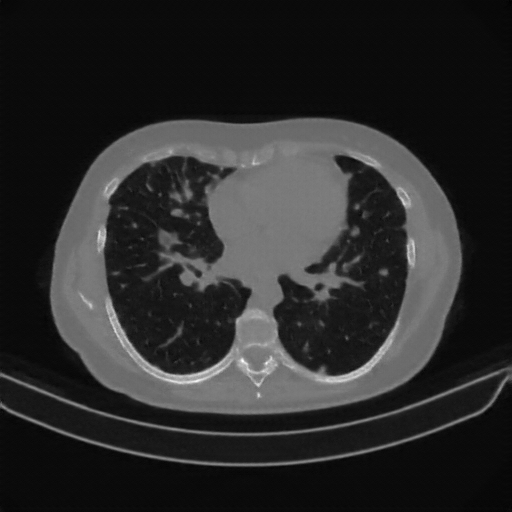

Original NATIVE CT scan (input)

No window - Raw intensity values

Lung window (WL -600, WW 1500 β†’ Low βˆ’1350, High +150)

Mediastinum window (WL 40, WW 400 β†’ Low βˆ’160, High +240)